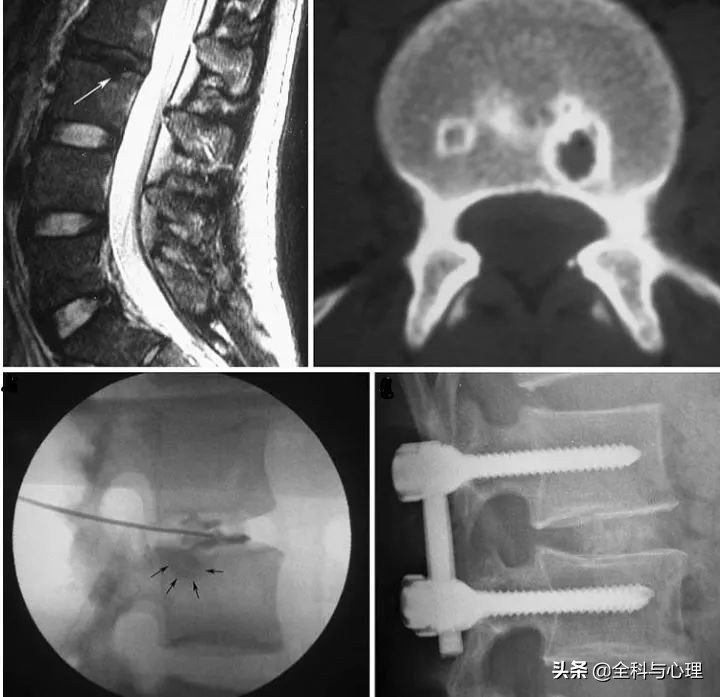

图示许莫氏结节(箭头所指),椎间盘造影后提示许莫氏结节为疼痛来源后行腰椎融合术